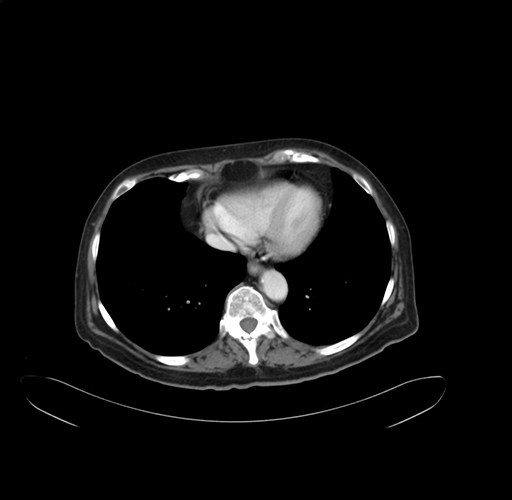

Pre-Chemo: Axial Venous